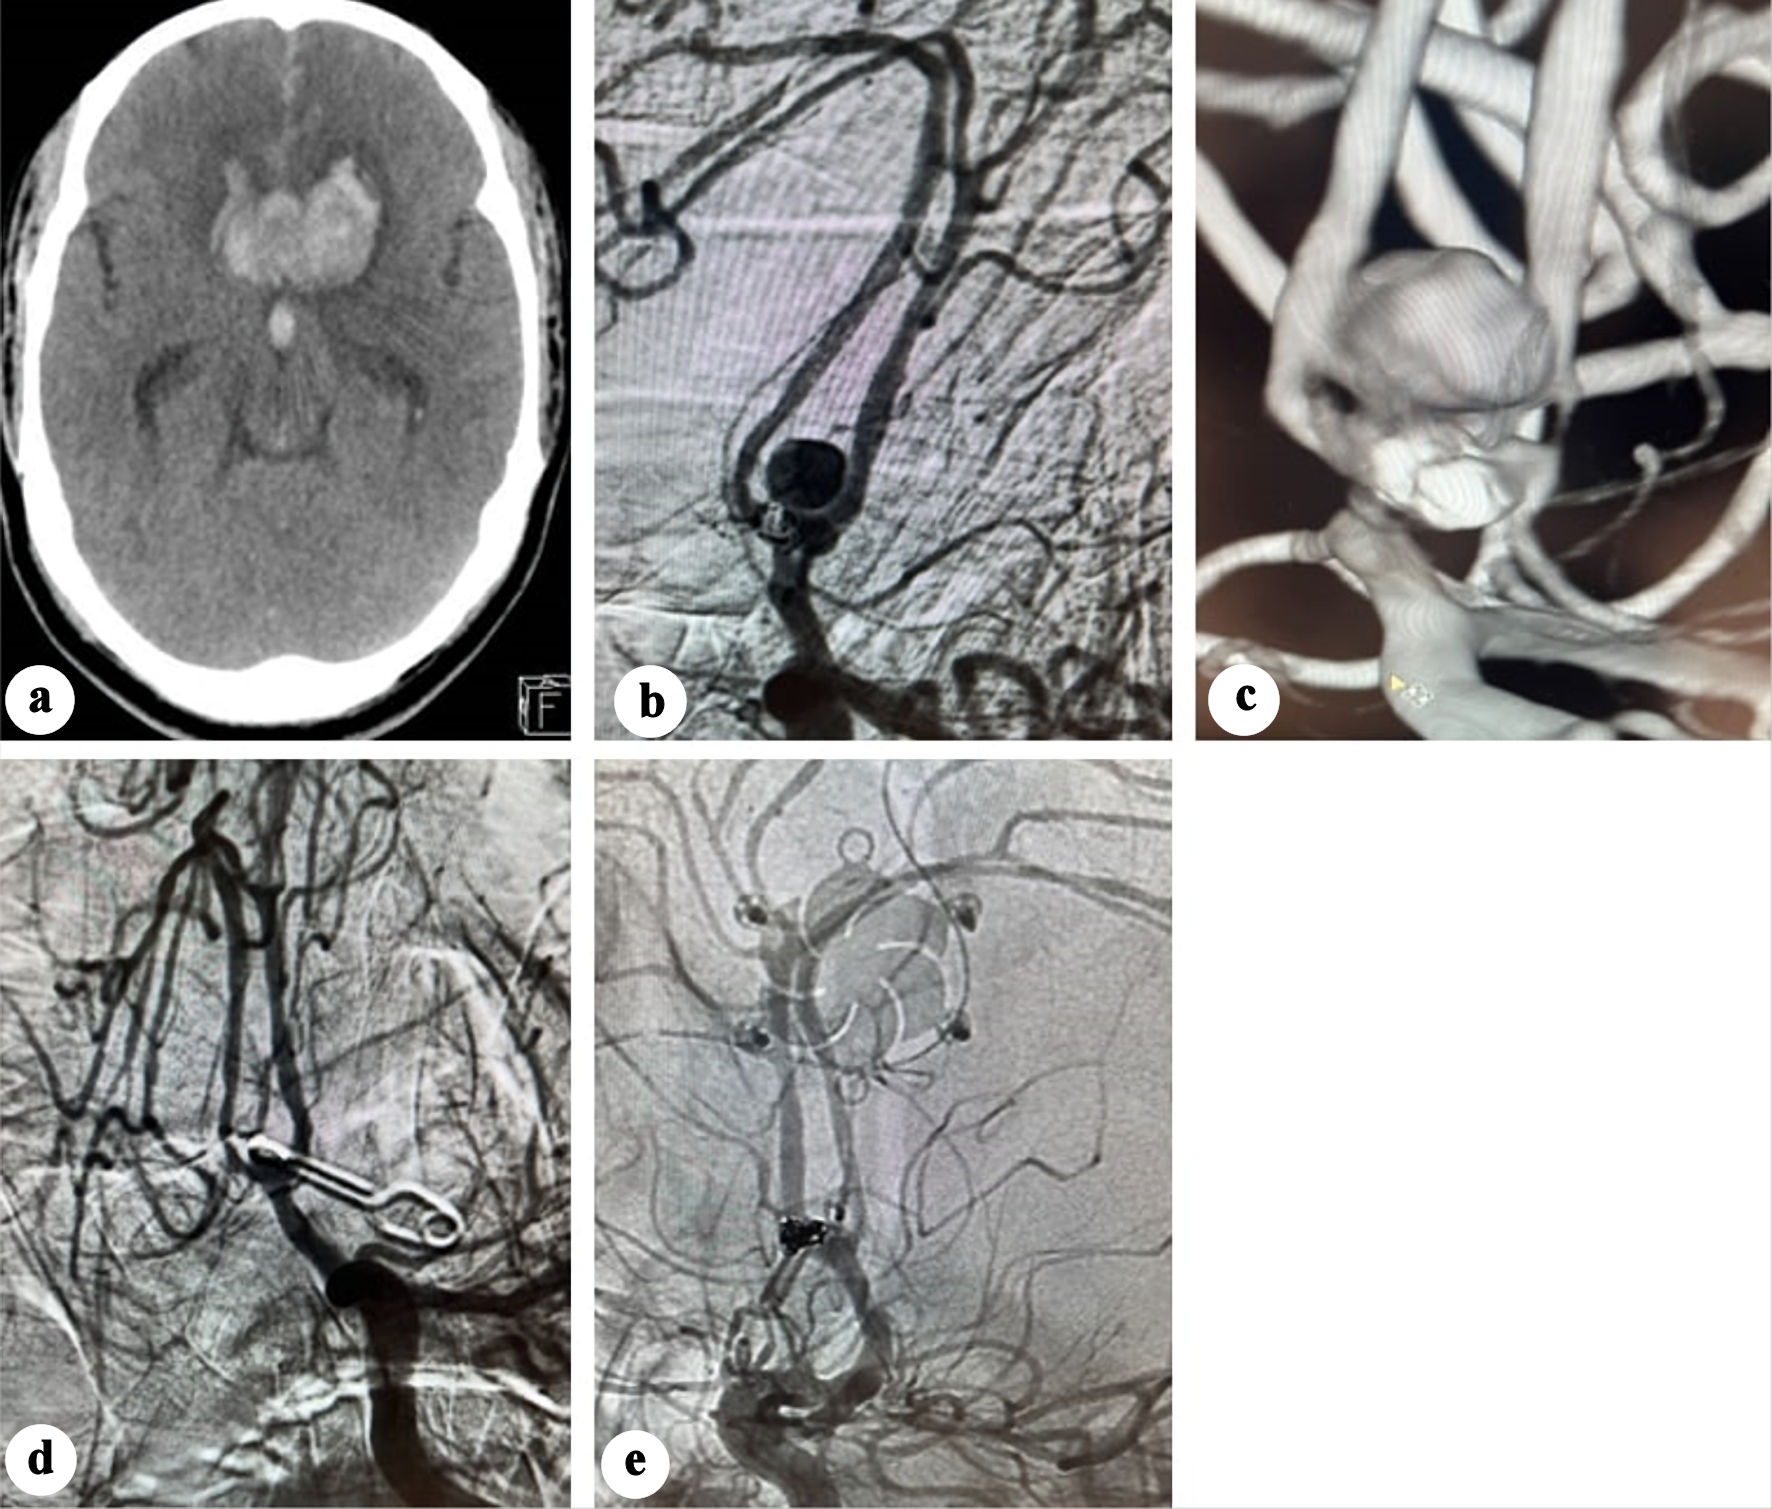

On day 10 post-coiling, the patient had another seizure episode along with decreased consciousness level (GCS 8). CT demonstrated significant rebleed with expansion of the interhemispheric hematoma reaching 38 mm in transverse axis, associated with intraventricular hemorrhage (Fig. 3a). Emergent 2D and 3D angiography identified an 8 mm pseudoaneurysm arising from the posterosuperior ACoA wall, while the coiled aneurysm was morphologically unchanged (Fig. 3b-c).

Figure 3. (a) Plain CT showing significant enlargement of the interhemispheric hematoma. (b) Anteroposterior view angiography showing developing of a pseudoaneurysm. (c) Three-dimensional (3D) angiography showing the development of a pseudoaneurysm opposite the previously coiled aneurysm. (d) Post-clipping subtracted angiography showing disappearance of the pseudoaneurysm. (e) Post-clipping native subtracted angiography showing disappearance of the pseudoaneurysm. CT: computed tomography.

The pseudoaneurysm was clipped via a left pterional craniotomy, and an external ventricular drain was inserted. Intraoperatively, the pseudoaneurysm was observed as a contained hematoma. Due to the absence of a clearly identifiable neck, the clip was applied as close as possible to the ACoA. Indocyanine green angiography confirmed aneurysm exclusion with preservation of the ACoA patency. Twenty-four hours later, a conventional angiography confirmed disappearance of the pseudoaneurysm (Fig. 3d, e).

Eight days after clipping, the patient developed sudden headaches associated with right-side hemiplegia. CT, CTA, and CT perfusion showed a bifrontal parasagittal perfusion defect and recurrence of the clipped pseudoaneurysm (Fig. 4a), which was immediately treated with coiling under protection of balloon remodeling, and intra-arterial vasodilator infusion (Fig. 4b, c).

Figure 4. (a) CTA showing recurrence of the pseudo sac post clipping. (b) Native angiography showing recanalization of the pseudoaneurysm. (c) Subtracted angiography post coiling of the pseudoaneurysm. (d) Subtracted angiography showing early recanalization of the pseudoaneurysm base. (e) Native acquisition showing the flow diverter deployed in the left side. CT: computed tomography.

One week later, the GCS improved to 13, and he regained full motor recovery. Follow-up angiography 9 days post-coiling revealed early recanalization at the pseudoaneurysm base (Fig. 4d). Ticagrelor 180 mg, acetylsalicylic acid 300 mg were initiated as a loading dose, and a Silk Vista Baby flow diverter (Balt Extrusion, Montmorency, France) was deployed extending from the left A2 to left A1segment (Fig. 4e), covering the irregularity previously noticed in the left A1 segment. Dual antiplatelet regimen (90 mg ticagrelor twice daily (BID) and 100 mg acetylsalicylic acid) was continued for 10 months.